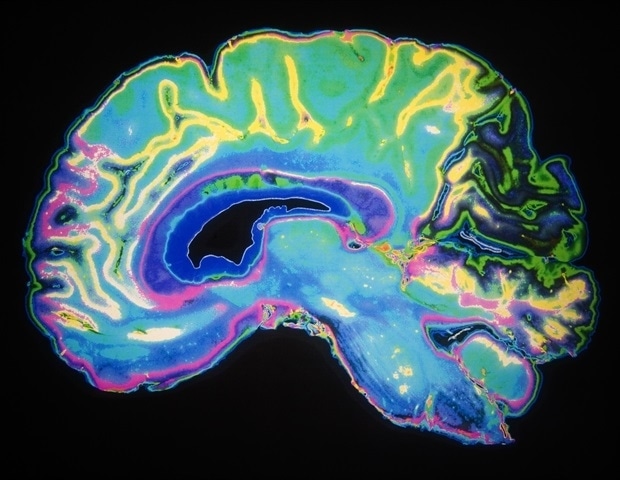

Μια νέα μελέτη από το Πανεπιστήμιο Griffith αποκαλύπτει ότι άτομα που πάσχουν από Μυαλγική Εγκεφαλομυελίτιδα/Σύνδρομο Χρόνιας Κόπωσης (ME/CFS) και Long COVID αντιμετωπίζουν διαταραχές στη σύνδεση του εγκεφάλου τους κατά τη διάρκεια απαιτητικών πνευματικών εργασιών. Η έρευνα, η οποία δημοσιεύθηκε σήμερα, χρησιμοποίησε τεχνολογία υπερυψηλού πεδίου MRI για να αναδείξει τη σημαντική μείωση της σύνδεσης σε συγκεκριμένες περιοχές του εγκεφάλου.

Η συγκεκριμένη έρευνα υποστηρίζει αυτό που πολλοί ασθενείς με ME/CFS και Long COVID βιώνουν: η γνωστική προσπάθεια δεν είναι απλώς κουραστική, αλλά μπορεί να έχει πραγματικές νευρολογικές επιπτώσεις. Η επαρκής ξεκούραση δεν είναι προαιρετική, αλλά απαραίτητη για την αποκατάσταση. Οι σαρώσεις έδειξαν αλλαγές στις περιοχές του εγκεφάλου που μπορεί να συμβάλλουν σε γνωστικές δυσκολίες, όπως προβλήματα μνήμης και δυσκολίες συγκέντρωσης.

Επιπλέον, το υπερυψηλό πεδίο MRI που χρησιμοποιήθηκε στην έρευνα είναι ένα από τα μόλις δύο διαθέσιμα στην Αυστραλία. Η έρευνα χρηματοδοτήθηκε από το ME Research UK και το Ίδρυμα Ιατρικής Έρευνας Stafford Fox.

Η μελέτη, με τίτλο “Distinct functional connectivity patterns in myalgic encephalomyelitis and Long COVID patients during cognitive fatigue: a 7 Tesla task-fMRI study”, δημοσιεύθηκε στο Journal of Translational Medicine.